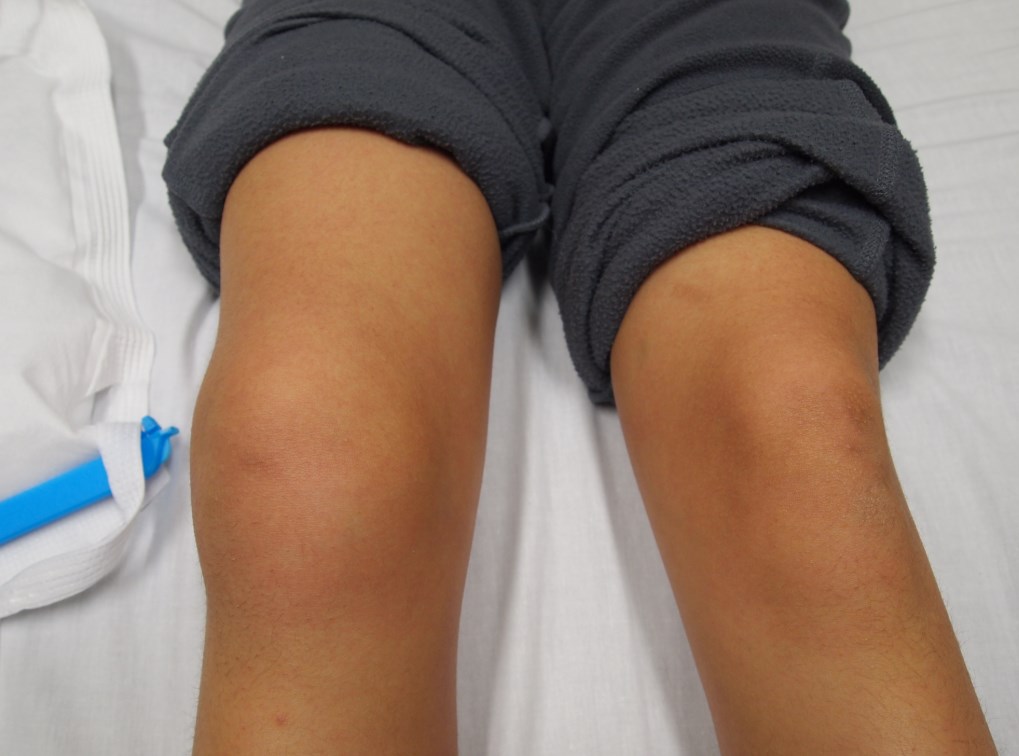

Такое опасное повреждение может внутрисуставным и внесуставным. В свою очередь, внутрисуставные повреждения делятся на открытые и закрытые. Они могут сопровождаться и другими повреждениями в виде разрыва связок, менисков, образования сосудисто-нервных пучков. Обнаружить перелом колена можно по следующей тревожной симптоматике:

- Отёчность околосуставных мягких тканей.

- Гематома под кожными покровами.

- Деформация суставного элемента.